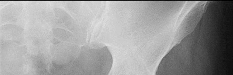

A 12-year-old obese boy presents with vague left thigh and knee pain. He is diagnosed with a Slipped Capital Femoral Epiphysis (SCFE) as seen in similar clinical scenarios.

During percutaneous in-situ fixation, unrecognized penetration of the guide wire into the hip joint occurs. What is the most likely specific complication resulting from this technical error?

Chondrolysis is a severe complication of SCFE characterized by rapid destruction of the articular cartilage. While it can occur idiopathically, its most established iatrogenic cause is unrecognized intra-articular hardware penetration. The 'approach-withdraw' fluoroscopic technique is required during pinning to assure pins are entirely intraosseous. Avascular necrosis (AVN) is usually due to damage to the epiphyseal blood supply (retinacular vessels) secondary to the initial displacement, forceful closed reduction, or posterosuperior pin placement.